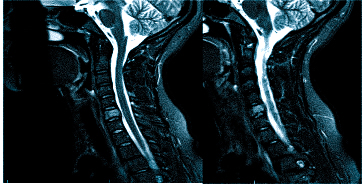

Важно! Если даже после подобной процедуры не станет ясна причина боли в голове, то потребуется дополнительная диагностика в виде МРТ, но уже позвоночника тела человека, а именно его шейного отдела.

Стандартным МРТ алгоритмом исследования при головных болях служит обследование 3 зон – МРТ головного мозга, МРТ сосудов головного мозга (МР-ангиография сосудов артериального круга мозга) и МРТ шейного отдела позвоночника. Неплохо дополнить этот набор исследований МР-ангиографией сосудов шеи. Каждый из перечисленных методов выполняет свои задачи. Очень редко назначают МР венографию сосудов головного мозга. Это связано с тем, что строение венозной системы очень индивидуально. Такие серьезные патологии вен, как тромбозы встречаются исключительно редко.

При шейном остеохондрозе грыжи не приводят к головным болям, они вызывают корешковый синдром, приводящий к болям и неприятным ощущениям (парестезии, слабости) в руке со стороны грыжи. Редко грыжа сдавливает спинной мозг или нарушает кровоснабжение его участка, приводя к миелопатии. Головные боли при остеохондрозе обусловлены нестабильностью в шейном отделе и болезненным напряжением мышц.

МРТ. Т2-зависимая томограмма. Сагиттальный срез. Грыжа диска.